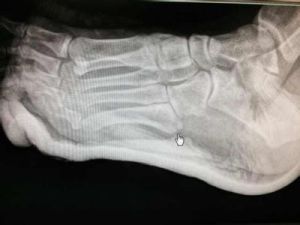

第五跖骨基底部骨折

第五跖骨基部撕脫骨折,腓骨短肌附著於第五跖骨基部結節處。足嚴重內翻扭傷可造成裂紋骨折或完全的撕脫骨折,X線照片檢查時應注意與兒童的正常骨骺相區別。第五跖...